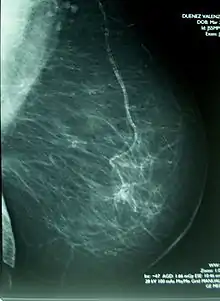

Mamografía

La mamografía o mastografía consiste en una exploración diagnóstica de imagen por rayos X de la glándula mamaria, mediante aparatos denominados mamógrafos (en dosis de alrededor de 0,7 mSv). Estos aparatos disponen de tubos de emisión de rayos X especialmente adaptados para conseguir la mayor resolución posible en la visualización de las estructuras fibroepiteliales internas de la glándula mamaria.

La capacidad de identificación de lesiones de mínima dimensión ha preconizado la utilización de la mamografía en revisiones sistemáticas para detectar tumores antes de que puedan ser palpables y clínicamente manifiestos (cribage mamográfico). Este diagnóstico, efectuado en una fase muy precoz de la enfermedad, suele asociarse a un mejor pronóstico de curación, así como a la necesidad de una menor agresividad del tratamiento para el control del cáncer.

Los radiólogos usan un método estándar para interpretar y comunicar los resultados de la mamografía, que actualmente se considera el idioma universal en el diagnóstico de la patología mamaria. Cuando detectan una lesión sospechosa de cáncer, la clasifican dentro de una categoría de BI-RADS (Breast Imaging-Reporting and Data System), las primeras etapas I y II son benignas, la III es probablemente benigna, mientras la IV y V aumenta la probabilidad de que sean malignas. Este sistema permite estandarizar la terminología del informe mamográfico y categorizar las lesiones estableciendo el grado de sospecha y asignar la actitud a tomar en cada caso. En muchas ocasiones la mamografía puede revelar lesiones malignas sin que estas se palpen clínicamente.[9][10]

La mamografía da falso negativo (no hay cáncer) al menos de un 10 %. Esto es parcialmente debido al oscurecimiento por tejidos densos, o muy densos que ocultan el cáncer, y a que la apariencia del cáncer en mamogramas tiene un gran solapeo con la apariencia de tejidos normales.